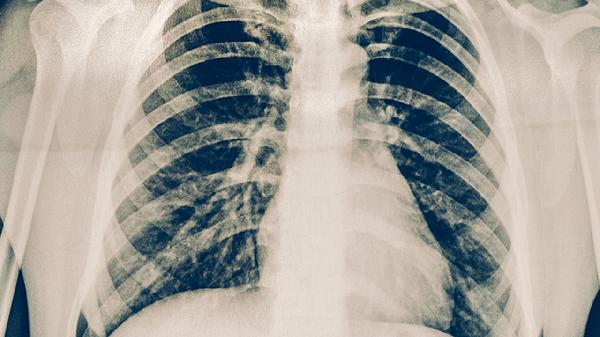

肺炎患者治疗期间需按医嘱定期复查胸部影像学检查,评估治疗效果。即使症状缓解也不可擅自停药,需完成整个疗程。康复期间应避免剧烈运动,注意休息。如出现持续发热、呼吸困难加重等症状,应立即就医。